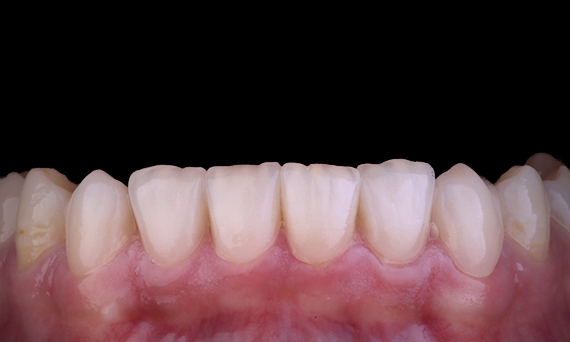

Los médicos de todas partes de Australia y Nueva Zelanda comparten amablemente presentaciones relevantes, interesantes y, a veces, desafiantes para los pacientes, junto con su selección de materiales y métodos para optimizar los resultados de sus pacientes.

En Dentsply Sirona, cada día destacamos a profesionales dentales de todo el mundo para que brinden a millones de pacientes un mejor cuidado dental y hagan sonreír a las personas. Nuestro enfoque de caso clínico se trata de compartir estas sonrisas, que los médicos de Australia y Nueva Zelanda han creado, con la comunidad dental en general.